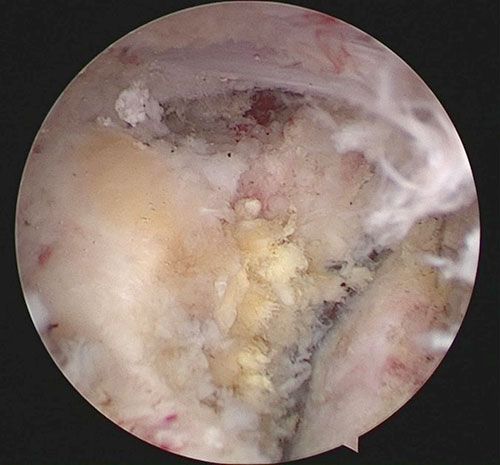

内镜下寰枢关节松解、瘢痕切除

寰枢椎处于颅颈交接区,是连接生命中枢的要塞,过去国内外多建议采用前后入路联合手术治疗,但传统的经口咽入路创伤大、易感染、并发症多,给患者及家属带来巨大的痛苦。随着现代医学技术的不断发展,在以内镜技术为代表的技术辅助下,难复性寰枢椎脱位的手术方案国内外虽有报道,但大多局限于零星病例的尝试。本次内镜辅助下经口咽入路进行前路松解,使原需广泛显露的手术切口简单化,内镜下的操作更为精细、安全、快捷。团队陈崇、叶勇裕医师通过组织耳鼻喉科、麻醉科、重症医学科、口腔科、营养科等多学科会诊、讨论后,手术如期执行,在神经电生理王良泽医师的监护下,首先行麻醉下牵引,仍然无法复位。郑晓青副主任医师具备多年的内镜操作经验,仅20分钟就完成内镜下的寰枢关节松解、复位,再通过后路螺钉的提拉,滑脱的寰椎成功“解剖”复位。